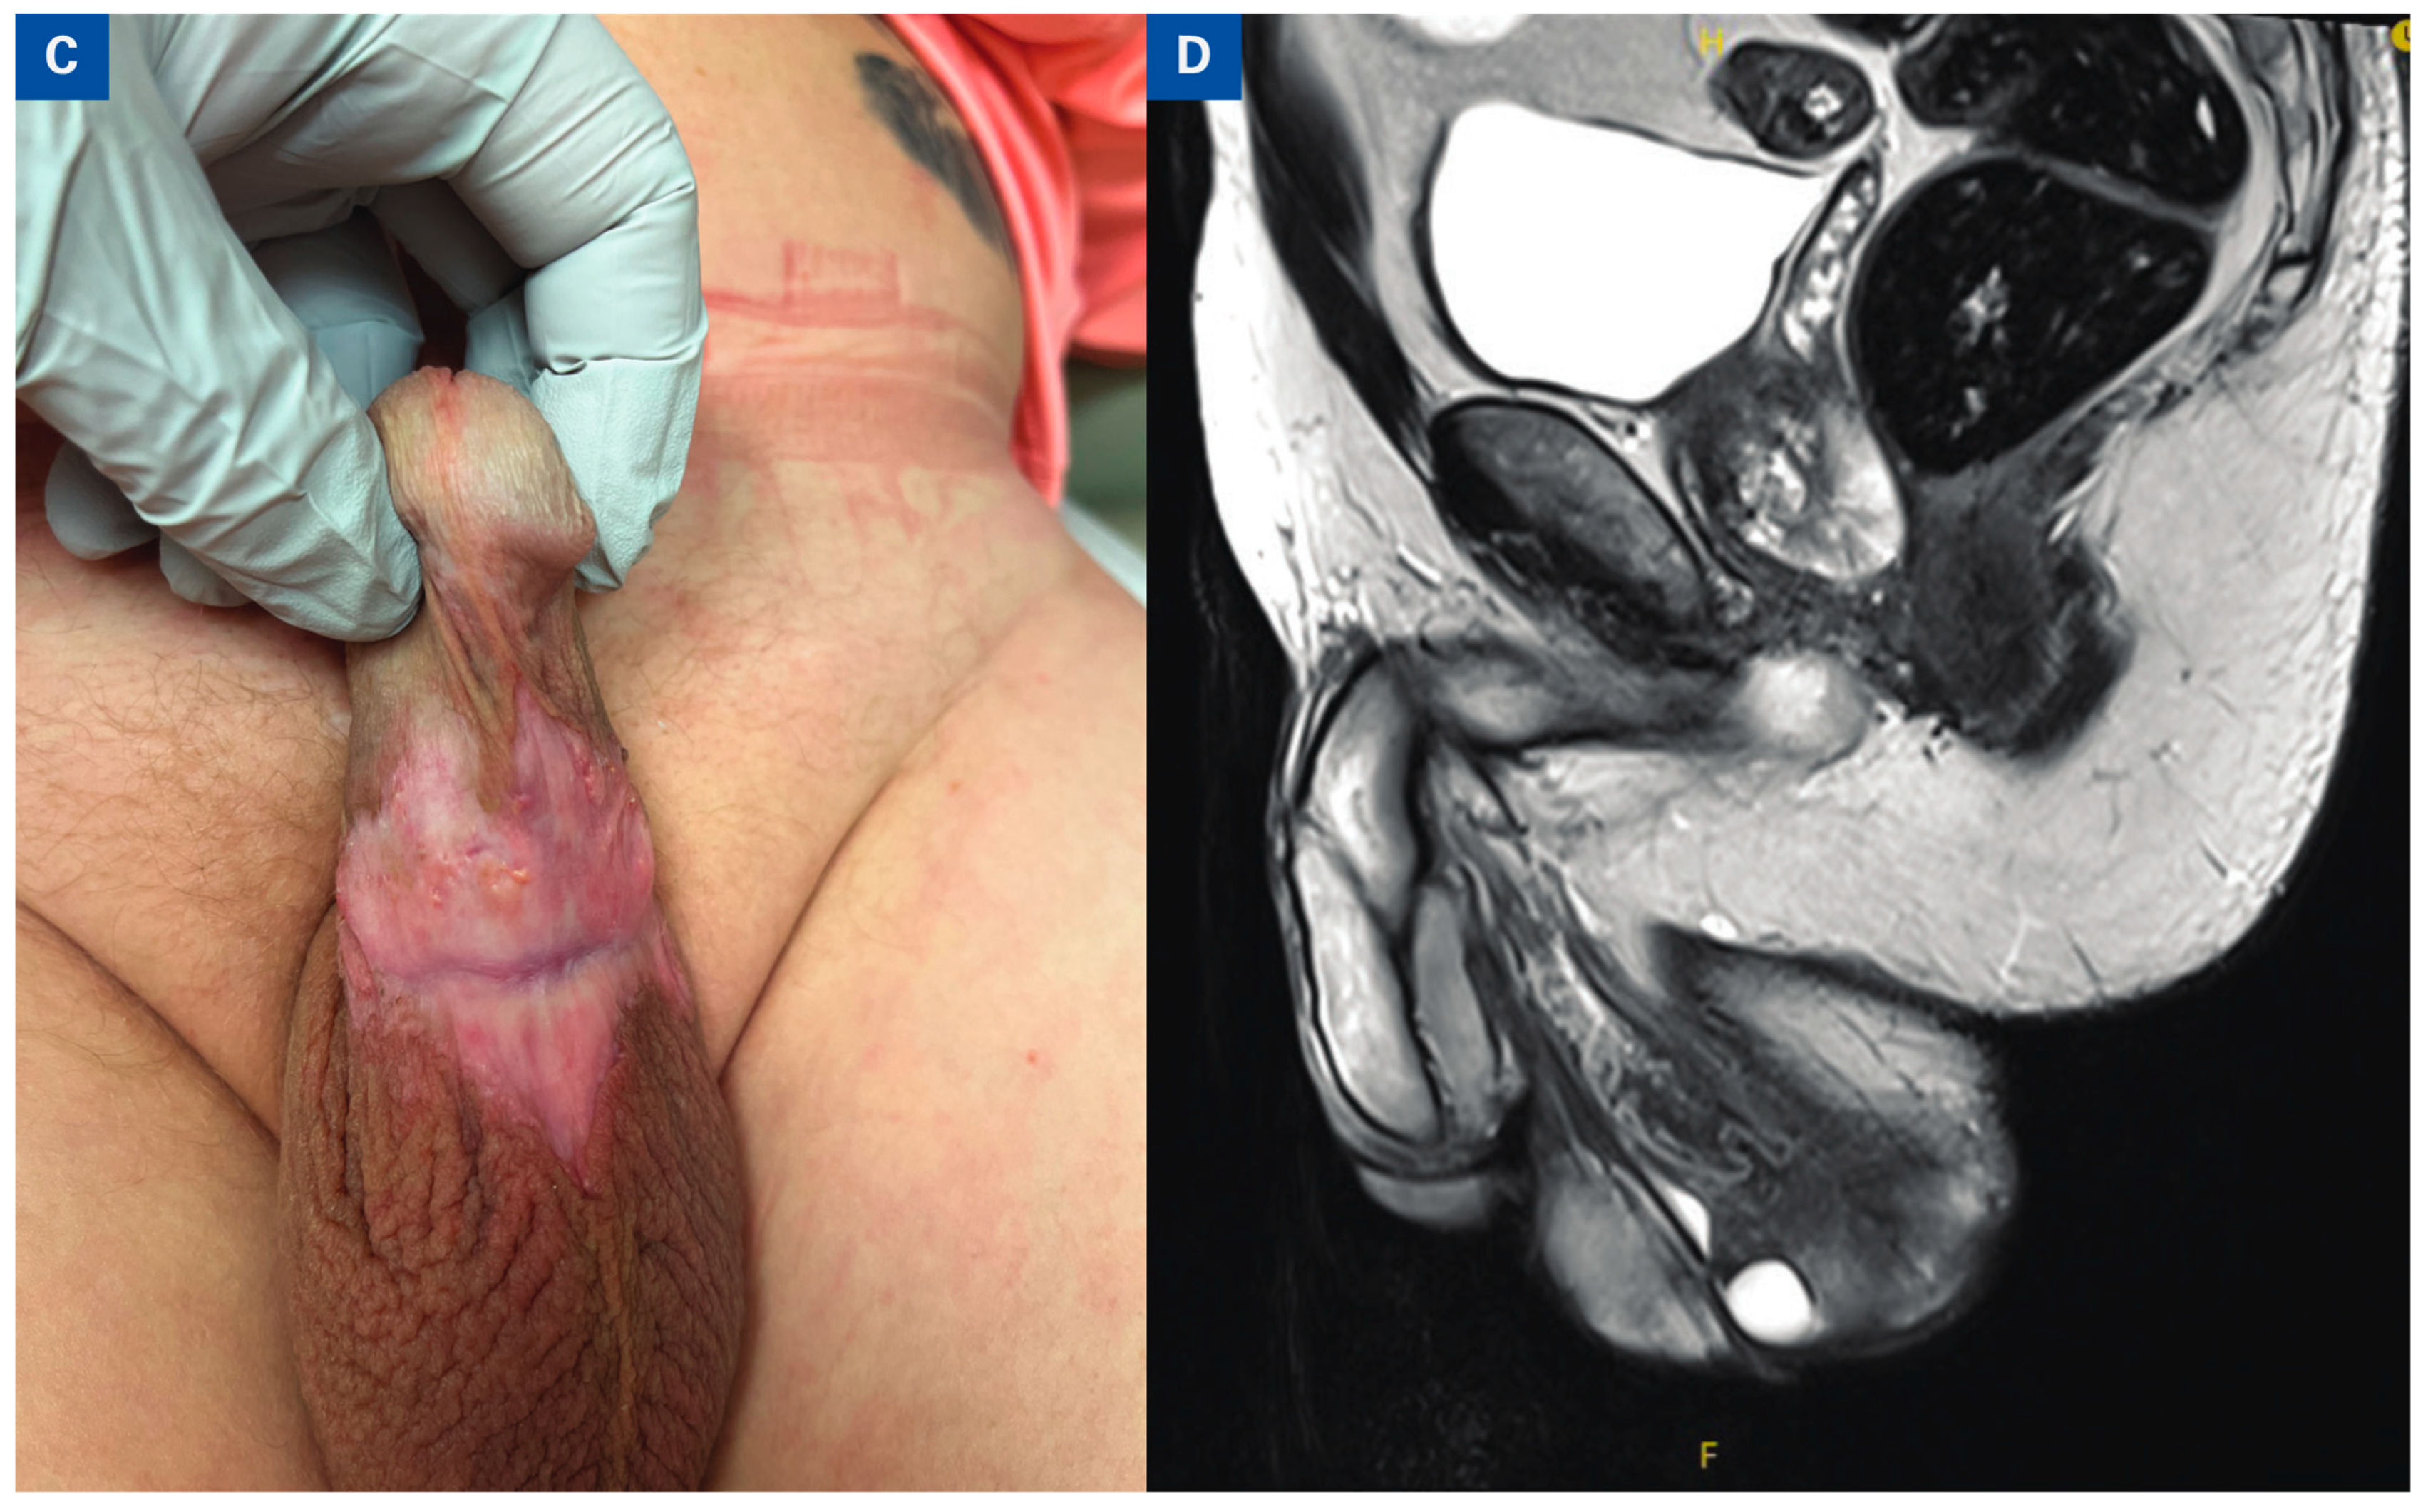

Representative photo of the penile lesion (A) On initial presentation. (B) Pre-treatment sagittal and axial MRI demonstrating penile mass with effacement of the corpus spongiosum. (C) Penile lesion status post 3 cycles paclitaxel, ifosfamide, and cisplatin (TIP) Chemotherapy. (D) Post-treatment MRI images with resolution of primary penile tumor.

Additional MDT discussions led to recommendation for induction paclitaxel, ifosfamide, and cisplatin (TIP) chemotherapy due to limited treatment options. The patient underwent 4 cycles of TIP chemotherapy without major adverse events resulting in a complete response (Figure 1C,D). The patient underwent 28 fractions of external beam radiation to the iLNs. At most recent follow-up he has no evidence of disease.